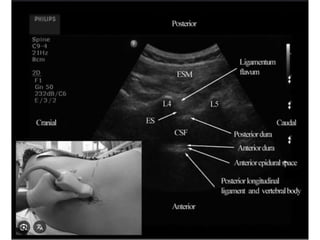

• US can identify anatomical landmarks and the depth of the

epidural space.

• It also allows for needle visualisation and epidural catheter

advancement within the epidural space in neonates and infants.

• The ability of US to produce an image is impeded by bone, and

therefore, with increasing age and increased ossification, less of the

spinal column contents can be observed.

• Because of this fact, imaging of the spine in neonates can be done

with the transducer in the midline longitudinal position; however, in

infants and older age groups, a paramedian longitudinal approach is

used to obtain a view through the interlaminar space.

• Paramedian longitudinal and the intervertebral axial planes

provide the best view of the spinal anatomy but the ultrasound

window size decreases with increasing age due to ossification.